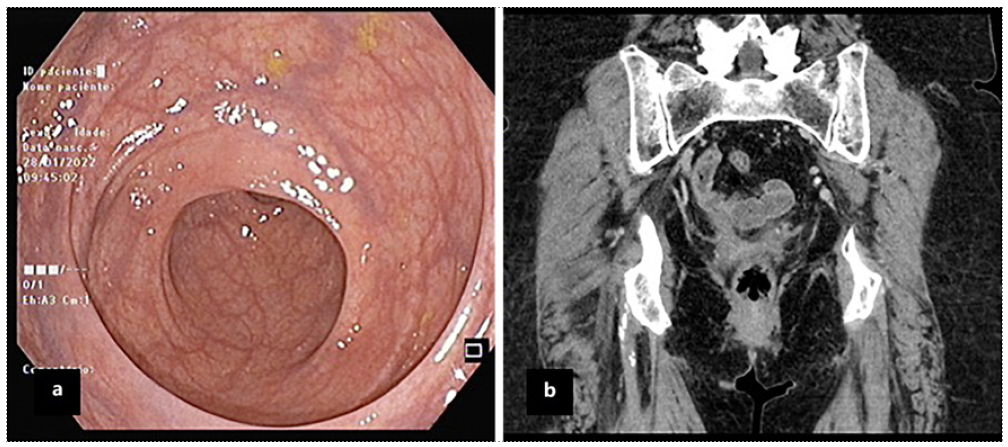

An abdominal and pelvic computerized tomography was performed, revealing an intramural collection containing hydroaeric levels in the right rectal wall, with a maximum diameter of 7 cm, compressing the rectal lumen (Fig. 2). The lower gastrointestinal bleeding and endoscopic findings were thus interpreted in the context of a rectal mural hematoma, communicating with the rectal lumen. The patient under-went conservative treatment, with complete reabsorption of the hematoma 2 months after surgery, which was confirmed by cross-sectional imaging and colonoscopy (Fig. 3).

Fig. 3 Colonoscopy (a) and computed tomography (b) images confirming complete rectal hematoma resolution.